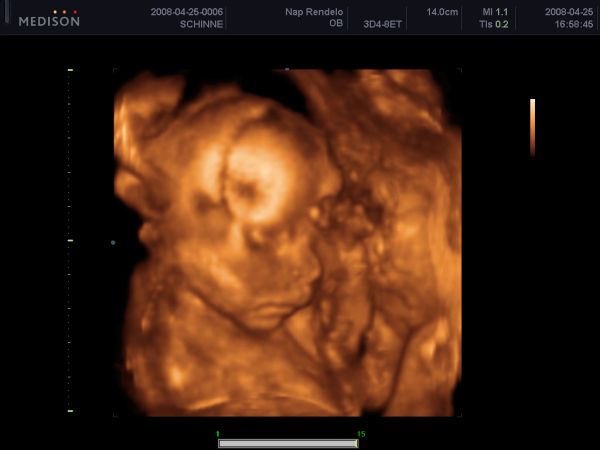

Csak egy gyorsra jöttem. Tegnap megvolt az uh, tényleg kisfiú :D :D

Dobok képet.

Itt már aludt: Kép

Ezen nagyon komolyan gondolkodik :lol:

Kép

szóval az első képen gondolkodik, a másodikon alszik...